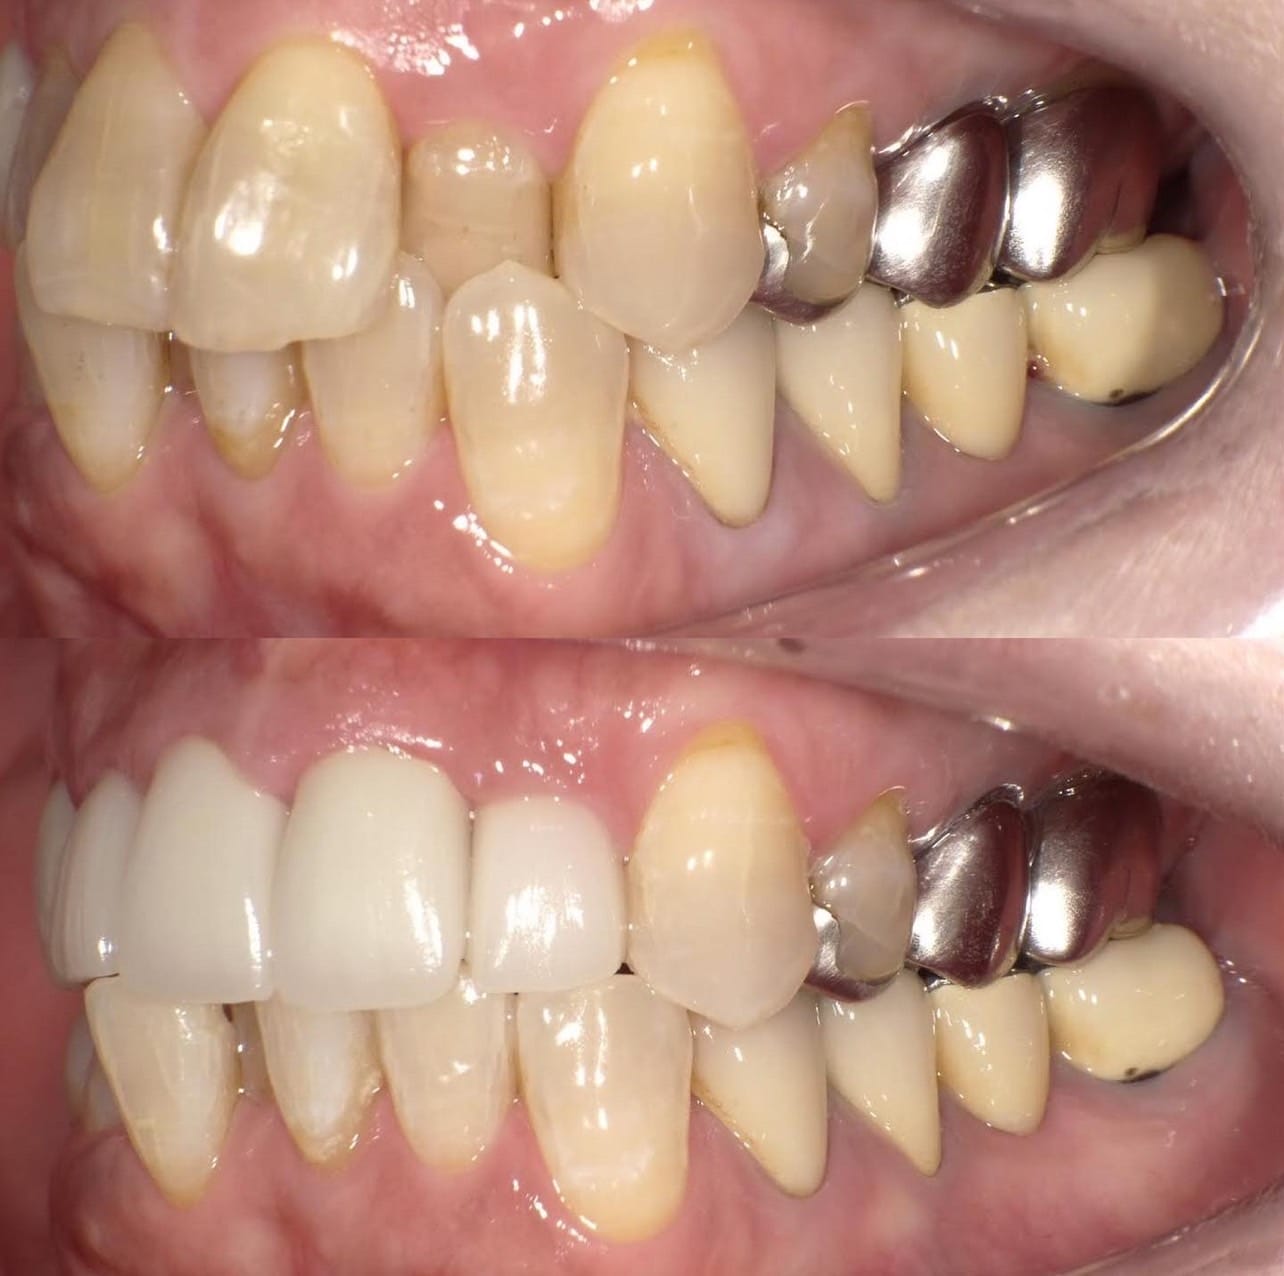

Case011 – インプラント

前医でインプラントの埋入角度が悪く、インプラント周囲炎になってしまった患者様の症例です。

インプラントが虫歯になることはありませんが、インプラント周囲炎というインプラントの歯周病にはなります。

インプラント周囲炎の主な原因は汚れ(菌)と力です。このように斜めに埋入されているインプラントは、真っ直ぐ埋入されているものに比べて汚れも溜まりやすく、噛む力も斜めにかかってしまうため、インプラント周囲炎になるリスクが大幅に高くなります。

この患者様は内側の骨が大幅に溶けてしまっていたので、前のインプラントを撤去して、骨を再生させると同時にインプラントを正しい位置と角度で埋入し直しました。溶けてしまっていた骨が治っていることもレントゲンでご確認いただけるかと思います。

インプラントは「どこの位置にどのような角度で入れるか」によって、一生使い続けられるかどうかの期待値が大きく異なります。値段だけを基準にクリニックを決めるのではなく、信用できる歯医医師と治療を進めることをお勧めします。

担当 理事長 佐藤悠野